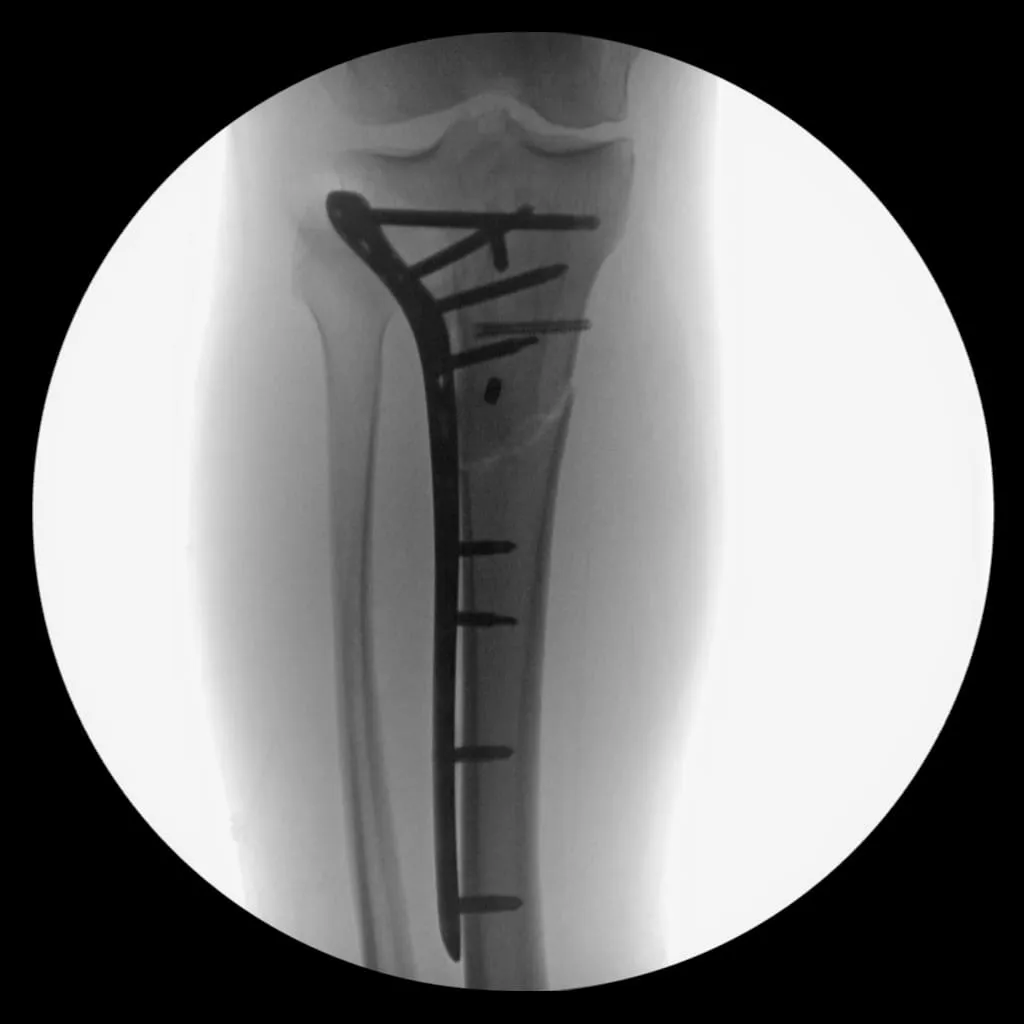

Nine days later, I underwent surgery to install additional hardware to support the fracture. Here is the x-ray from my first post-op appointment.

This marked the third time in eight years that I found myself on crutches and unable to put weight through my leg for 2.5 months. I had to undergo physical therapy three times a week to regain the ability to walk. Four months after surgery, at the end of April, I took my first running steps on a treadmill at physical therapy.